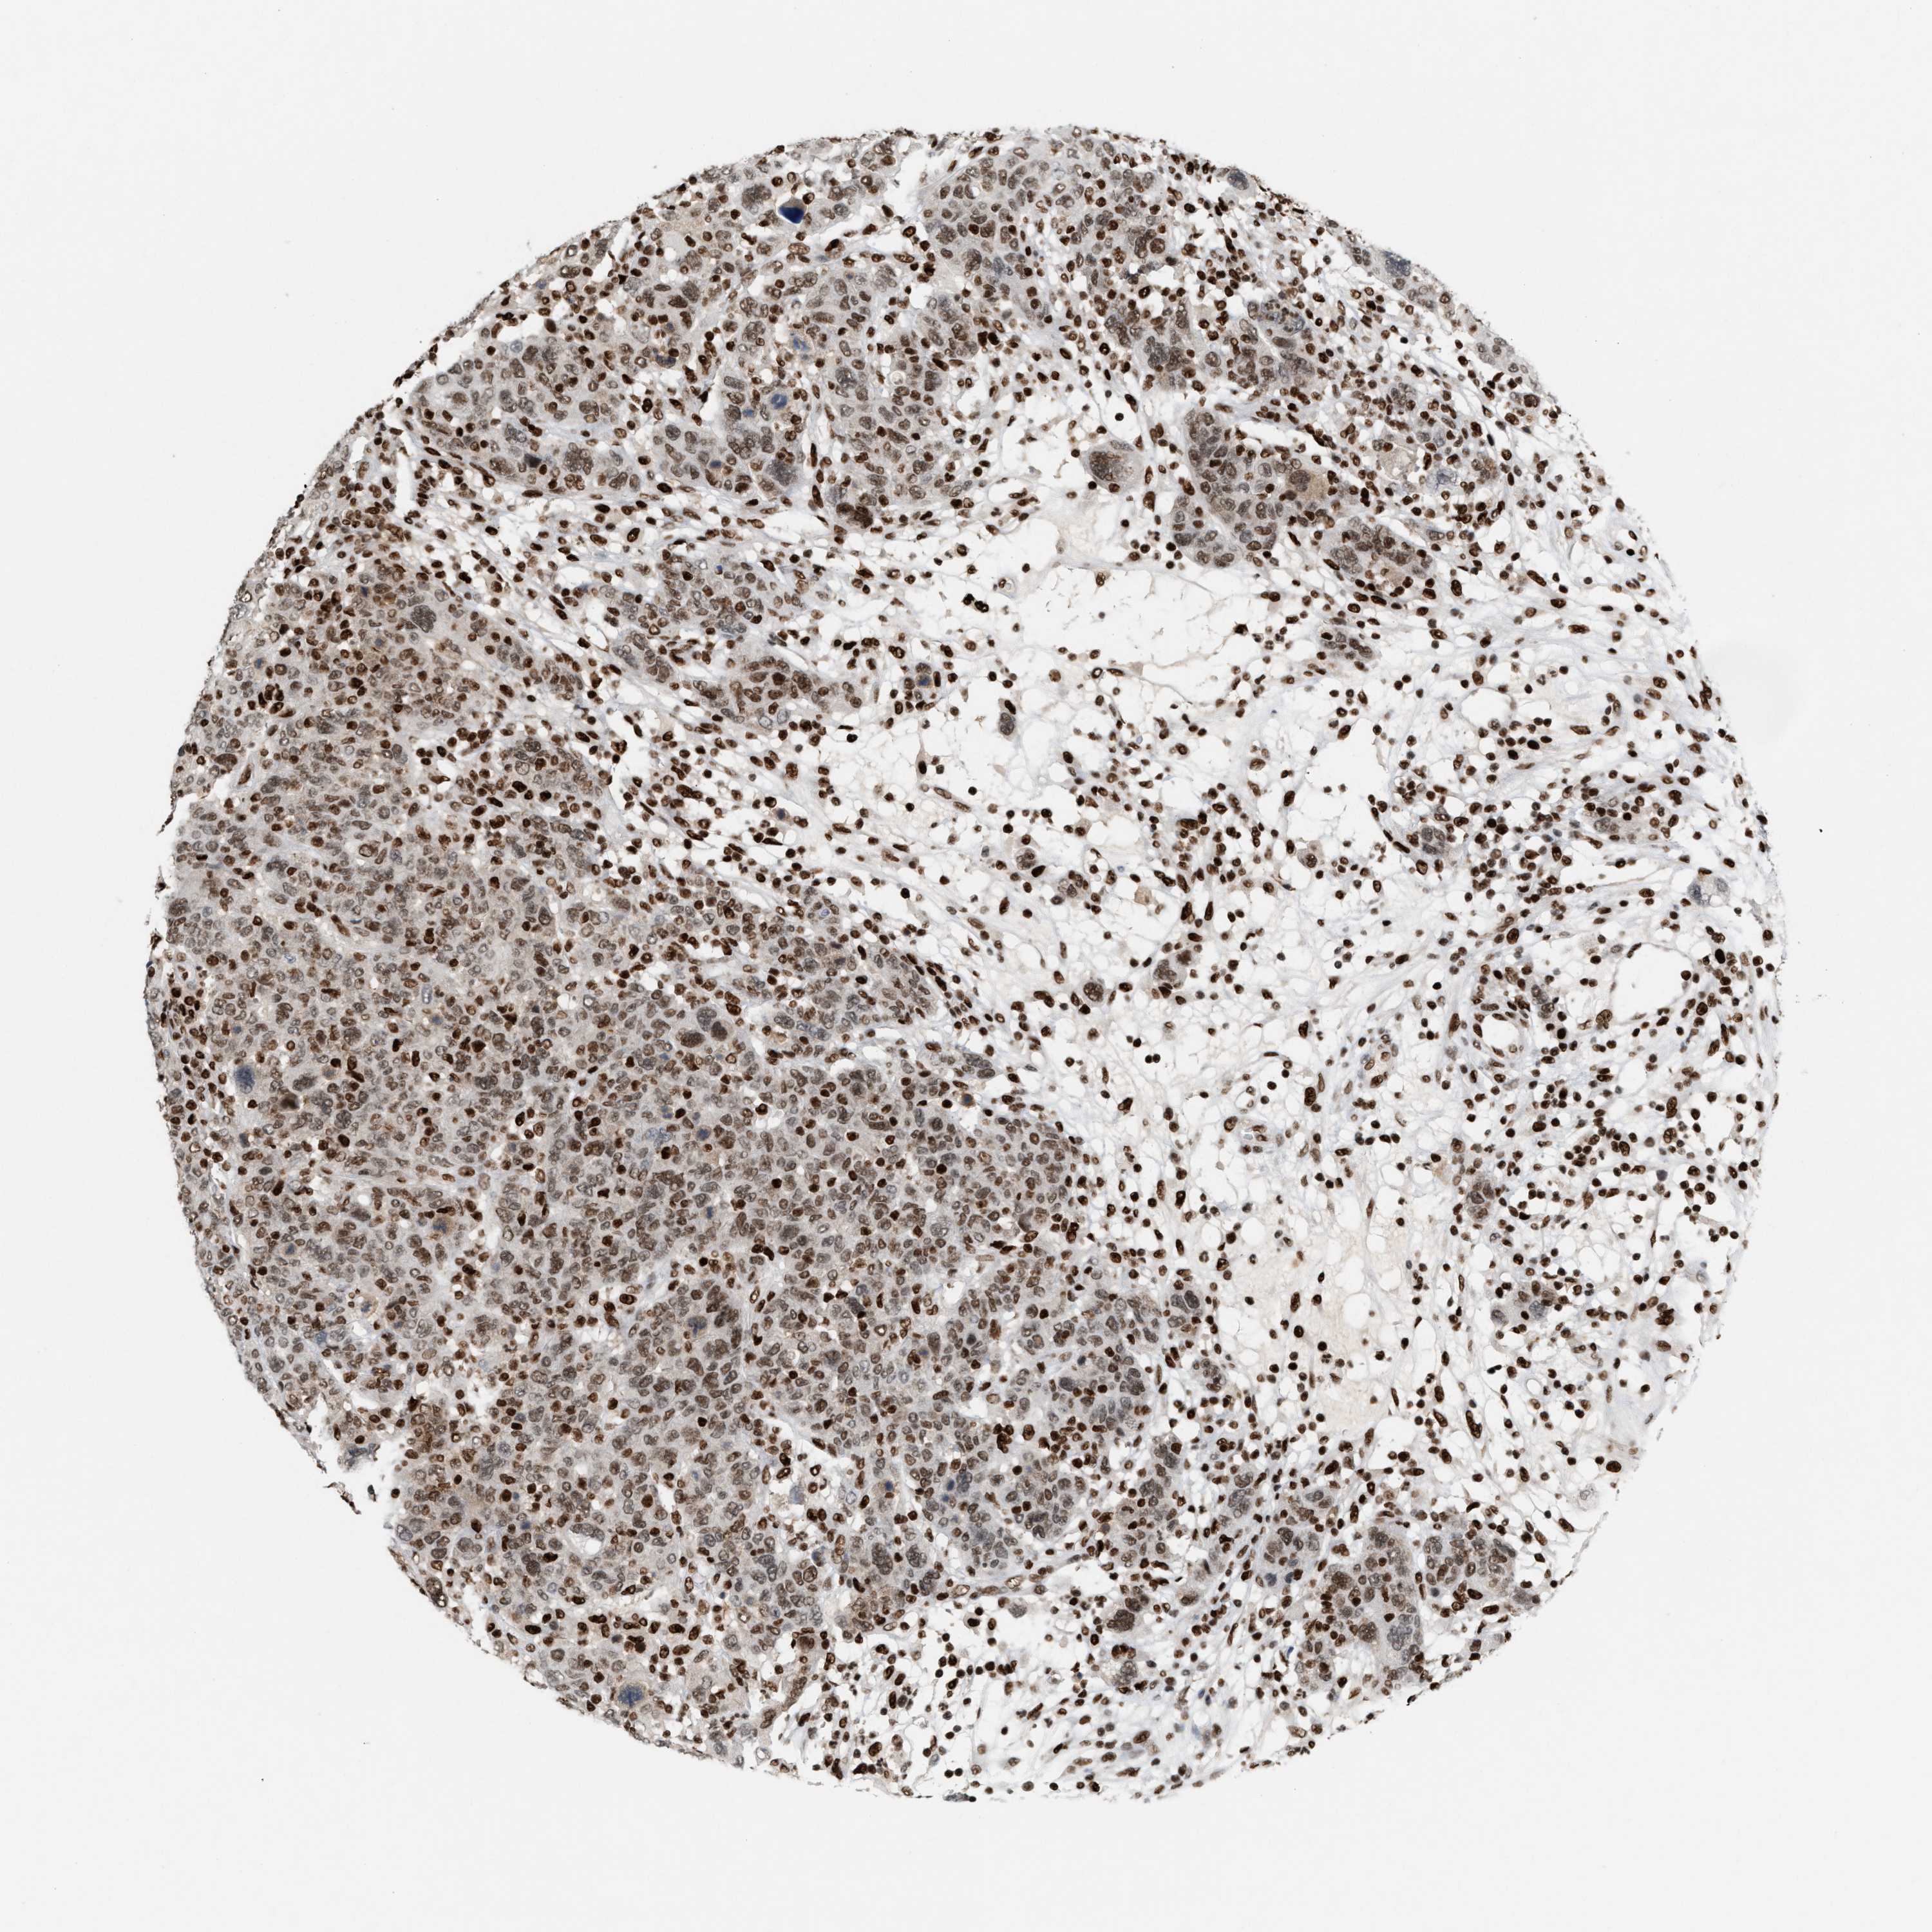

CANCER BREAST CANCER Show tissue menu

BRCA TCGA BRCA VALIDATION PROTEIN EXPRESSION

ANTIBODIES

AND

VALIDATION